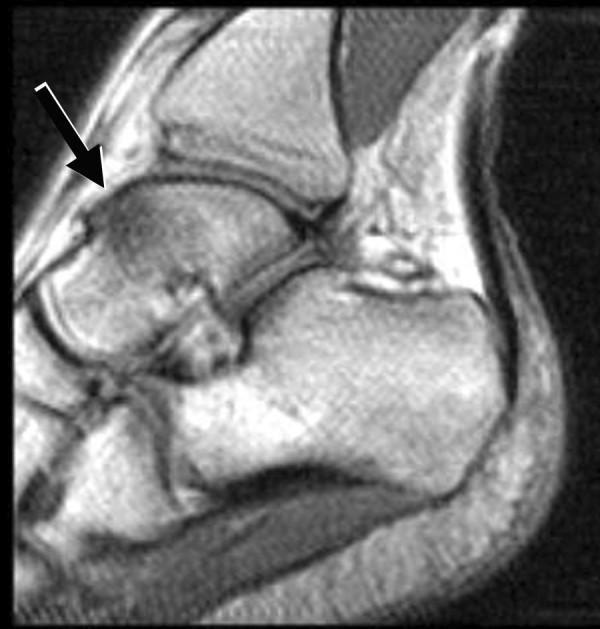

Bone marrow edema was seen only in the talus, and was a common finding, observed in nine of the twelve ankles imaged (75%) and was associated with pain in all cases. On fluid-sensitive sequences, bone marrow edema was ill-defined and centered in the talar neck or body, although in three cases it extended to the talar dome. No apparent gender predilection was noted. No occult stress fracture could be diagnosed. A moderately strong correlation (phi = 0.77, p= 0.0054) was found between edema and pain in the study population.

仅在距骨中发现骨髓水肿,这是一个常见的表现,在12个成像踝关节中的9个(75%)观察到,并且在所有病例中均与疼痛相关。在液体敏感序列上,骨髓水肿边界不清,集中在距骨颈或距骨体,尽管在3例中延伸至距骨穹窿。未发现明显的性别倾向。未诊断出隐匿性应力性骨折。在研究人群中,水肿与疼痛之间存在中度强相关性(phi = 0.77,p = 0.0054)。